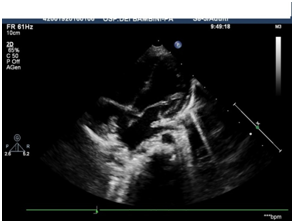

Our patient, an extreme preterm twin, was born at the 27th week of gestation with multiple complication. In fact, at birth the newborn was affected by respiratory distress due to surfactant deficiency, anemia, sepsis and posthemorrhagic hydrocephalus. Therefore, at the age of four month he underwent ventriculoperitoneal (VP) shunt. However, after two months from the first surgical intervention, it was necessary to replace the catheter due to infection. Successively, at seven months of life, a malfunction of the VP shunt made necessary proceeding to a surgical removal of the entire VP shunt system and to the positioning of a ventriculoatrial (VA) shunt with OMNISHUNT 80-120 INTEGRA valve. When the infant was 11 month old, hospitalization in our department was necessary because of a fever resisting home-based therapy. We proceeded with an echocardiogram that showed a thrombotic formation on the catheter tip in the right atrium, thus it was decided to begin an anticoagulant therapy with a dose of 1.7 mg/kg of low-molecular-weight-heparin (LMWH) every 12 hours. The ineffectiveness of this treatment was demonstrated by a significant increase of the thrombotic massed,which became jutting over the tricuspid plane and by the onset of an obstacle to the discharge of the superior vena cava (SVC) (max gradient of 25 mmHg, average gradient of 18-20 mmHg) (Figure 1 & 2).

Figure 1: TTE, subcostal view.

Figure 2: TTE, apical view.